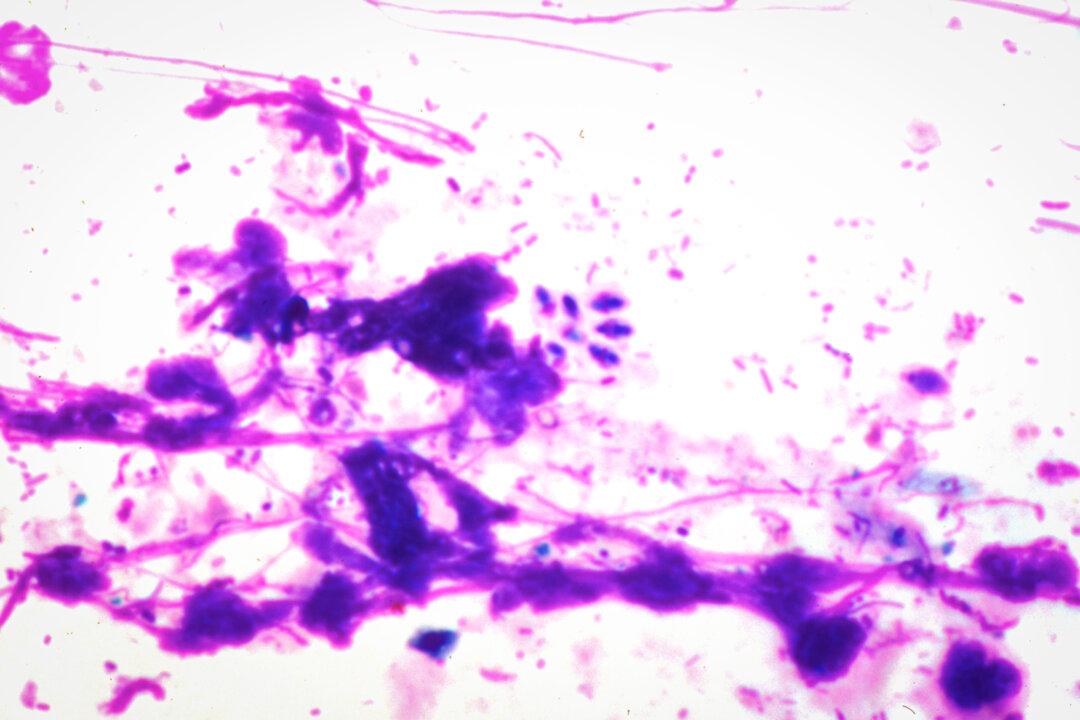

Clusters of T. gondii in bone marrow. (Cultura RM Exclusive/Michael J. Klein, M.D./Gettyimages)